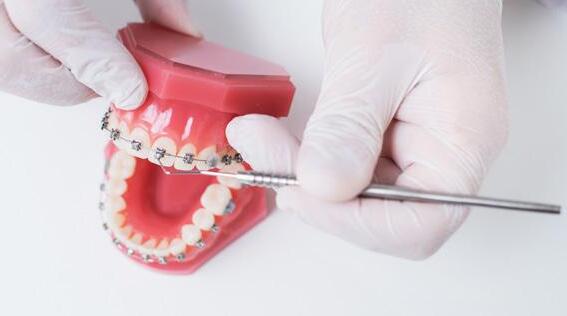

Los microtornillos ortodóncicos se utilizan como método de anclaje disminuyendo así la necesidad de colaboración de nuestros pacientes y obteniendo resultados más predecibles en nuestros tratamientos.

En el inicio del uso de estos aditamentos (TAD) se utilizaban con frecuencia los microtornillos intraalveolares que se colocan entre las raíces de los dientes entre otras localizaciones. Hoy en día se siguen utilizando, pero con la aparición de los microtornillos extraalveolares se reducen sus indicaciones, es decir, cada vez se emplean más porque presentan más ventajas en comparación con los interradiculares.1,2 Los microtornillos extraalveolares no solo resuelven el problema de anclaje sino que también consiguen tratar casos de extracciones sin tener que realizarlas gracias a la biomecánica que permiten.1,3 Se requieren microtornillos de mayor diámetro y longitud que los microtornillos interradiculares, entre 1.5 y 2 mm de diámetro y de 10 a 17 mm de longitud, en cambio los microtornillos interradiculares presentan un diámetro menor de 1 y 1.5 mm y longitud de 6 a 8 mm. Los

microtornillos extraalveolares están indicados para corregir una amplia variedad de maloclusiones complejas, en cambio los microtornillos interradiculares están indicados para corregir problemas concretos como: mesialización molar unilateral o bilateral, intrusión de incisivos y corrección de un plano oclusal asimétrico.2

Los microtornillos extraalveolares presentan una serie de ventajas frente a los interradiculares: menor riesgo de lesión de las raíces y ligamento periodontal, anclaje adecuado debido a una mayor cantidad de hueso cortical, tasa de fracaso mucho menor, inflamación de las encías en zonas no visibles, posibilidad de tratar casos complejos y con menor número de microtornillos, aplicación de fuerzas con vectores múltiples, modificación del plano oclusal e incisal, posición bucal de la cabeza del microtornillo que permite una correcta biomecánica, además de presentar mayor diámetro y longitud lo que favorece la estabilidad primaria.1,4,5,6